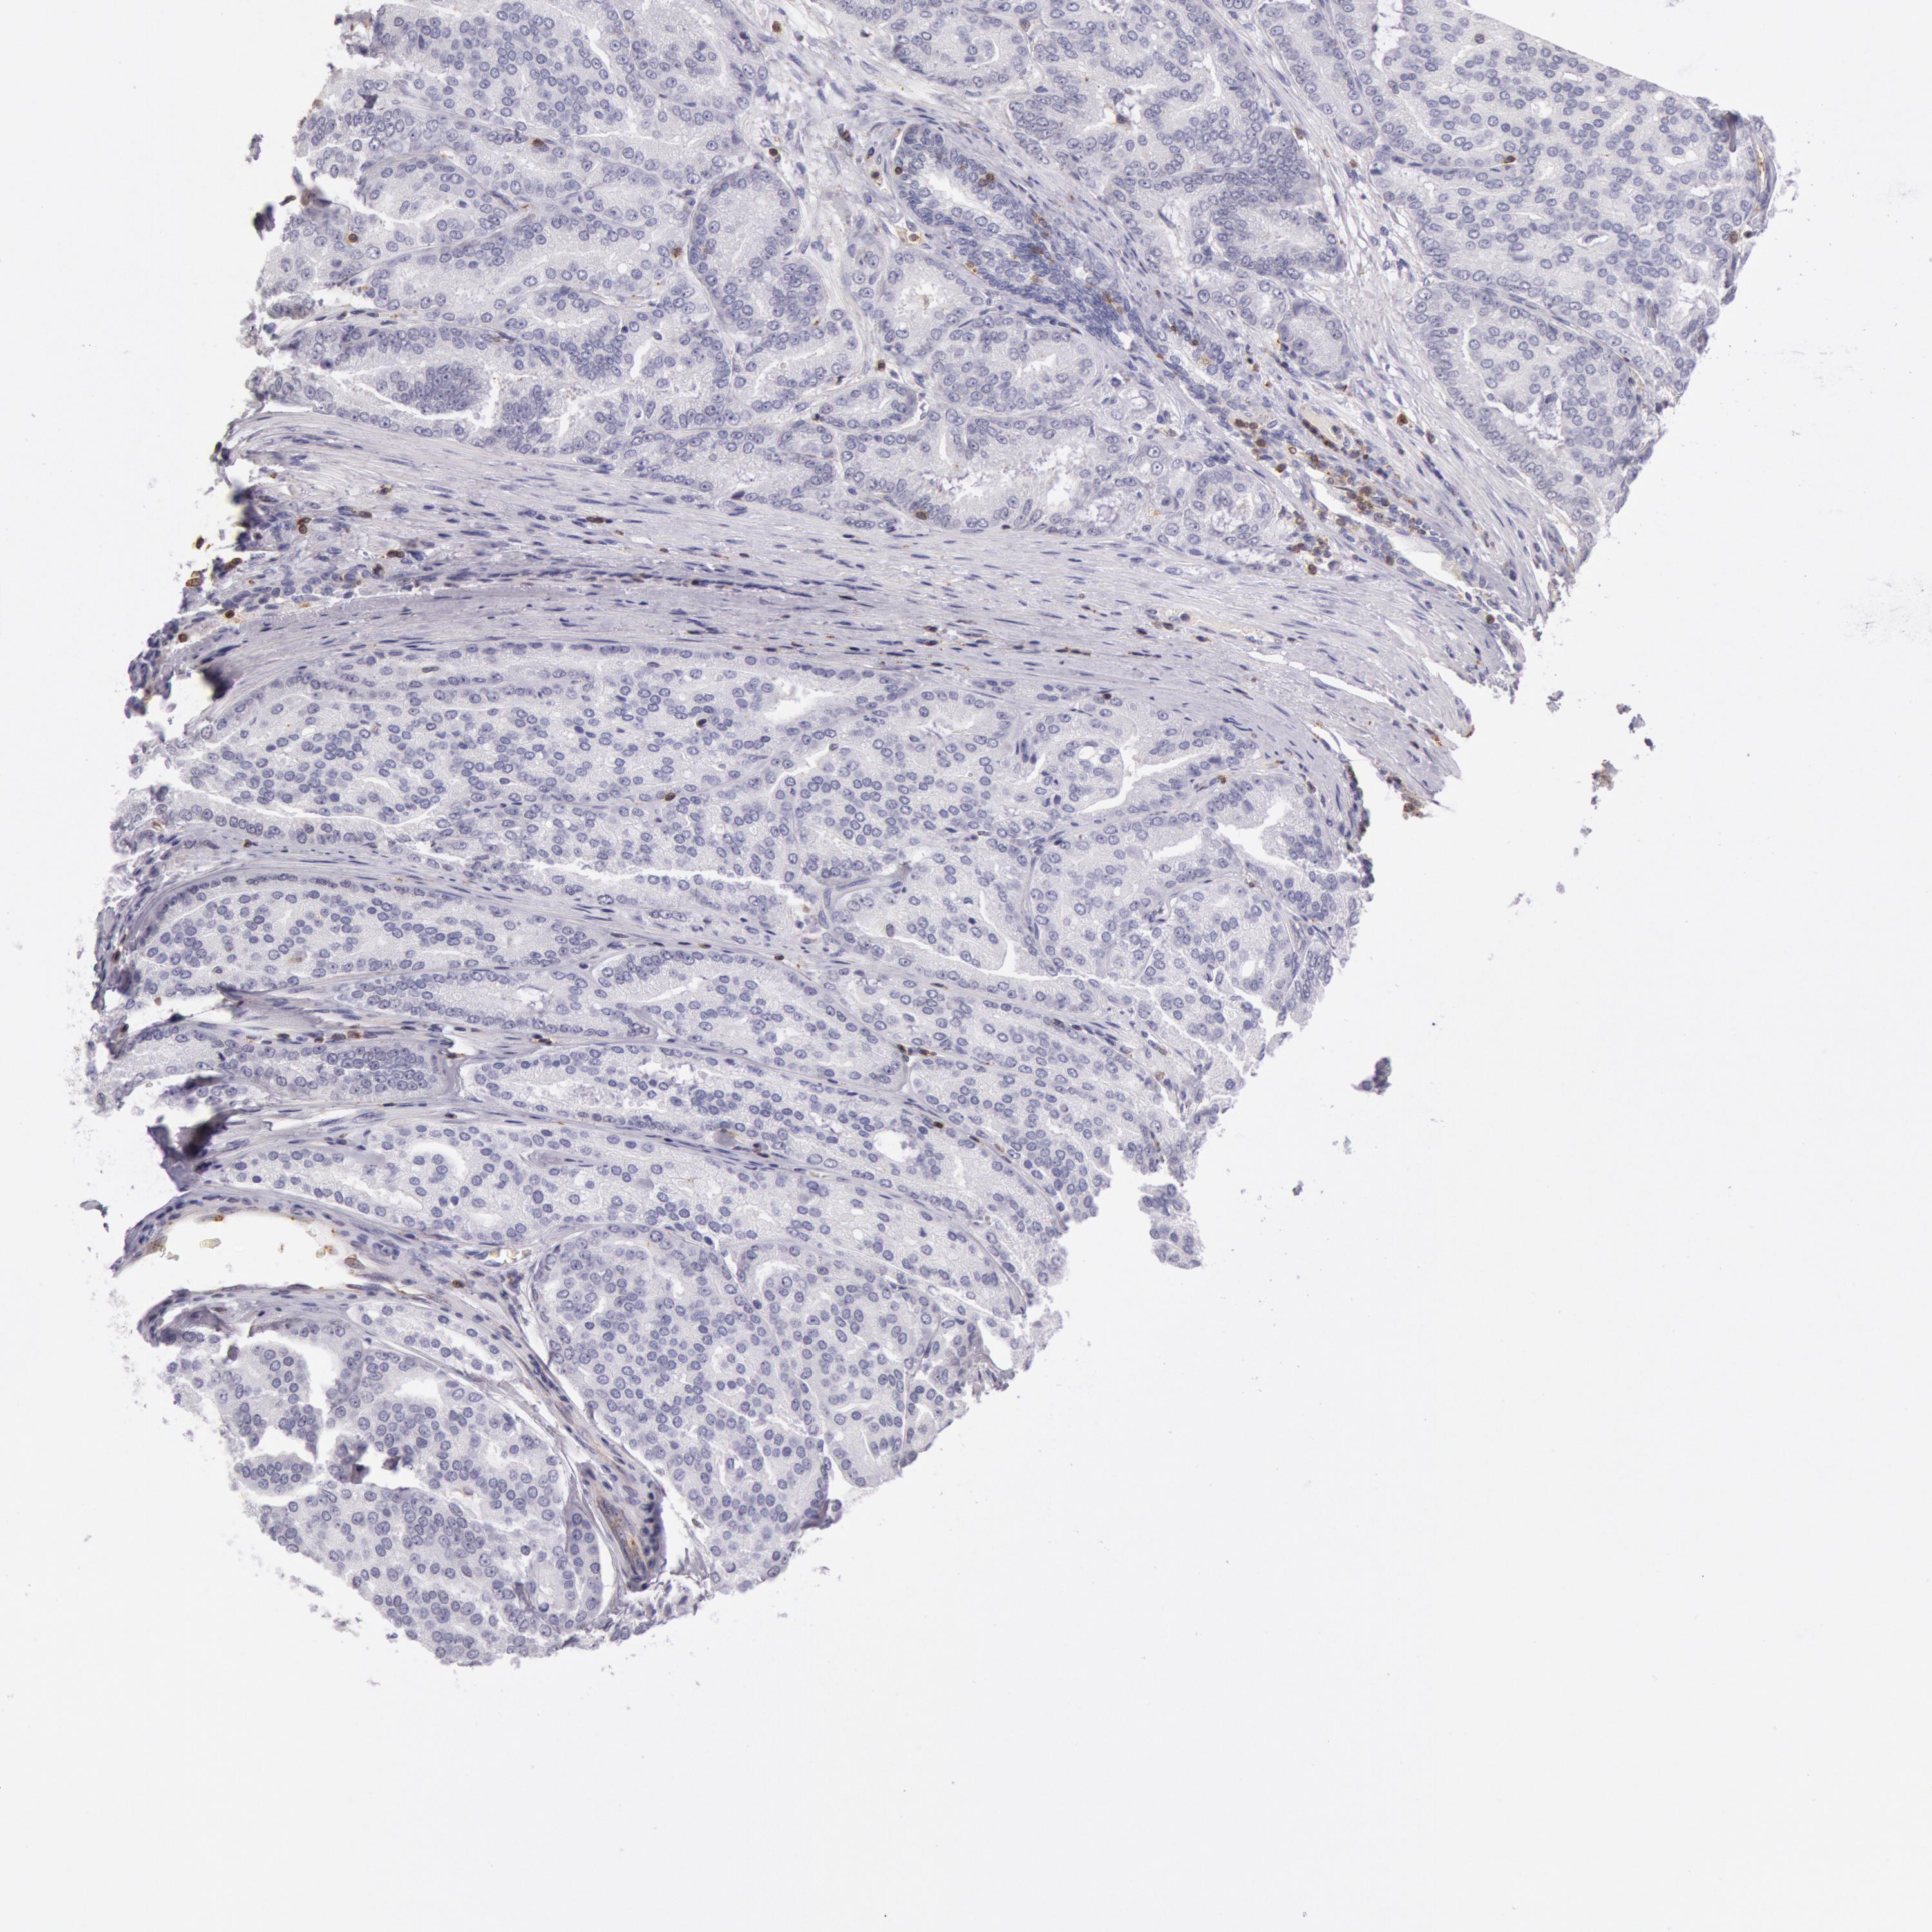

PROSTATE CANCER - Protein expressioni

A mouse-over function shows sample information and annotation data. Click on an image to view it in a full screen mode. Samples can be filtered based on level of antibody staining by selecting one or several of the following categories: high, medium, low and not detected. The assay and annotation is described here.

Antibody stainingi

Antibody staining in the annotated cell types in the current human tissue is reported as not detected, low, medium, or high, based on conventional immunohistochemistry profiling in selected tissues. This score is based on the combination of the staining intensity and fraction of stained cells.

Each image is clickable and will lead to virtual microscopy that enables deeper exploration of all samples and also displays staining intensity scores, fraction scores and subcellular localization as well as patient and tissue information for each sample.

Antibody HPA001275

Antibody CAB017442

Staining

High

Medium

Low

Not detected

Intensity

Strong

Moderate

Weak

Negative

Quantity

>75%

75%-25%

<25%

None

Location

Nuclear

Cytoplasmic/membranous

Cytoplasmic/membranous,nuclear

Adenocarcinoma, Medium grade

Adenocarcinoma, Low grade

Adenocarcinoma, High grade